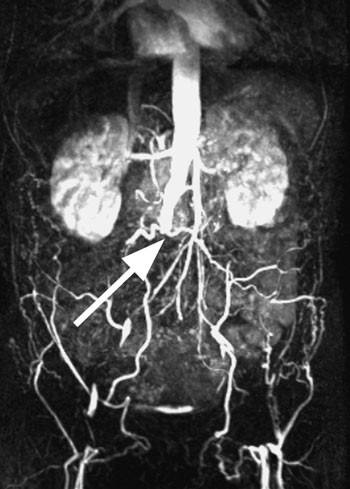

I perioden november 2005 til mars 2006 ble det ved Oslo vaskulære senter utført total laparoskopisk aortaoperasjon hos åtte pasienter med invalidiserende claudicatio intermittens grunnet uttalt aortoiliakal okklusiv sykdom (fig 1). Alle pasientene hadde type D-lesjon i henhold til TASC-inndelingen (Transantlantic Inter-Society Consensus) fra 2000, gjengitt i e-ramme 1 (5). Hos to pasienter ble det benyttet en talestyrt robotarm (AESOP) for styring av laparoskopet. Operasjonene ble utført i narkose, epiduralanalgesi ble anvendt kun hos de to første pasientene. Pasientene ble informert om prosedyren både muntlig og skriftlig, og alle forespurte ga skriftlig samtykke.